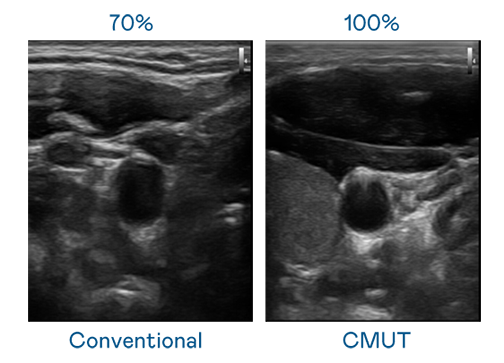

CMUT 技術是一種用電容式微機電元件來產生超音波訊號的技術。與傳統 PZT 壓電式技術相比,CMUT 頻寬增加 30%,更寬頻的超音波訊號讓影像解析度大幅提升,是實現高影像品質醫療超音波掃描、促進精準醫療發展的關鍵技術。

超音波影像的解析度高低,首先取決于探頭能發出的訊號頻寬。LEYU官網 CMUT 可提供高清晰的超音波訊號,提供高頻寬、高靈敏度、影像紋理細節更高的超音波影像,協助醫護人員縮短影像判讀時間及利用精準的醫療影像進行診斷。